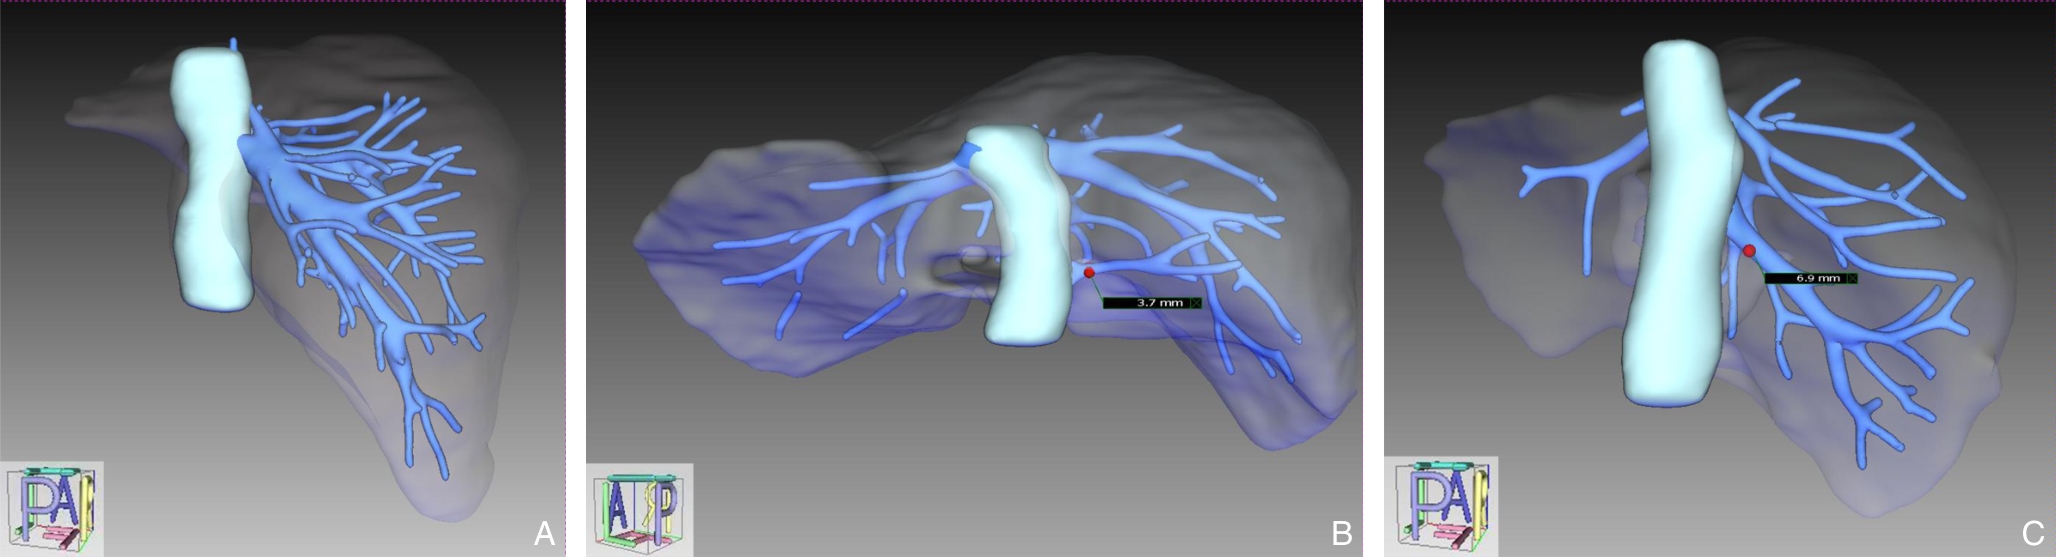

• Application of augmented reality navigation combined with indocyanine green fluorescence imaging in laparoscopic resection of central hepatic tumors

Abstract:Background and Aims Laparoscopic resection of centrally located hepatic tumors remains technically demanding due to the complex anatomical relationships with major vascular structures. Conventional intraoperative ultrasound or indocyanine green fluorescence imaging (ICG-FI) alone has limitations, particularly in visualizing deep anatomical structures. This study aimed to evaluate the clinical value of augmented reality (AR) navigation combined with ICG-FI in laparoscopic resection of central hepatic tumors.Methods A retrospective analysis was conducted on 38 consecutive patients who underwent laparoscopic resection of central hepatic tumors guided by AR navigation combined with ICG-FI between May 2022 and March 2025. Intraoperative navigation performance, surgical parameters, and perioperative outcomes were assessed.Results All 38 procedures were completed laparoscopically without conversion. The intraoperative tumor fluorescence detection rate was 100%. The mean operative time was (324.9 ± 132.4) min, and the median intraoperative blood loss was 400 (50-1 200) mL. The mean registration error was (6.3±0.6) mm. The median number of predicted and verified vessels was 6 (4-8) and 7 (5-10), respectively. R0 resection was achieved in all patients, with a mean surgical margin of (1.5±0.5) cm. The postoperative complication rate was 13.2%, with no severe complications such as intra-abdominal hemorrhage, gas embolism, or liver failure. The median postoperative hospital stay was 9 (4-20) days. During a median follow-up of 20 months, no tumor recurrence was observed.Conclusion The combined use of AR navigation and ICG-FI enables intraoperative prediction and verification of critical vascular structures and facilitates precise control of the transection plane in laparoscopic resection of central hepatic tumors. This technique improves surgical precision and safety and shows promising clinical potential.